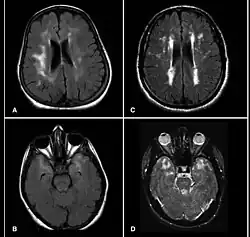

CADASIL charakteryzuje się: nawracającymi epizodami udarów podkorowych lub przemijającymi atakami niedokrwiennymi (TIA) u osób młodych przy braku klasycznych czynników miażdżycy, np. zaburzeń lipidowych lub nadciśnienia. Powtarzające się, często subklinicznie incydenty niedokrwienne (bez wyraźnych objawów zauważalnych przez pacjenta) prowadzą do rozległej leukoencefalopatii widocznej w badaniu MRI głowy w postaci zlokalizowanych głęboko małych zawałów jąder podstawy i istoty białej. Objawowe udary mogą się manifestować niedowładem kończynowym, niedowładem mięśni twarzy, zaburzeniami mowy, zaburzeniami świadomości. Często towarzyszą temu bóle głowy o charakterze migreny z aurą. Wraz z upływem czasu rozwija się na tym podłożu otępienie, głównie podkorowe i zespół rzekomoopuszkowy.

- MRI głowy (czulsze od badania TK)- wykazuje początkowo wieloogniskowe zmiany niedokrwienne w głębokich strukturach mózgu, a następnie rozległe uszkodzenie istoty białej, z zaoszczędzeniem tzw. włókien „U”. Obraz nie jest specyficzny.